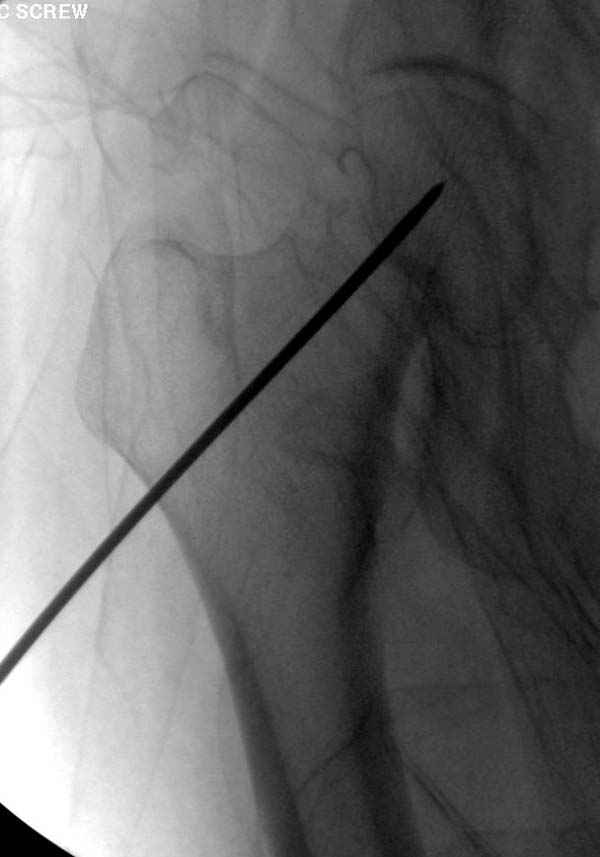

Профилактику дальнейшего раскола неполного перелома шейки провели тремя канюлированными шурупами.

Наверное речь идет насчет parallel guide из набора. Применяем по возможности всегда, но,

как видно на снимке, не всегда получается

паралельно.